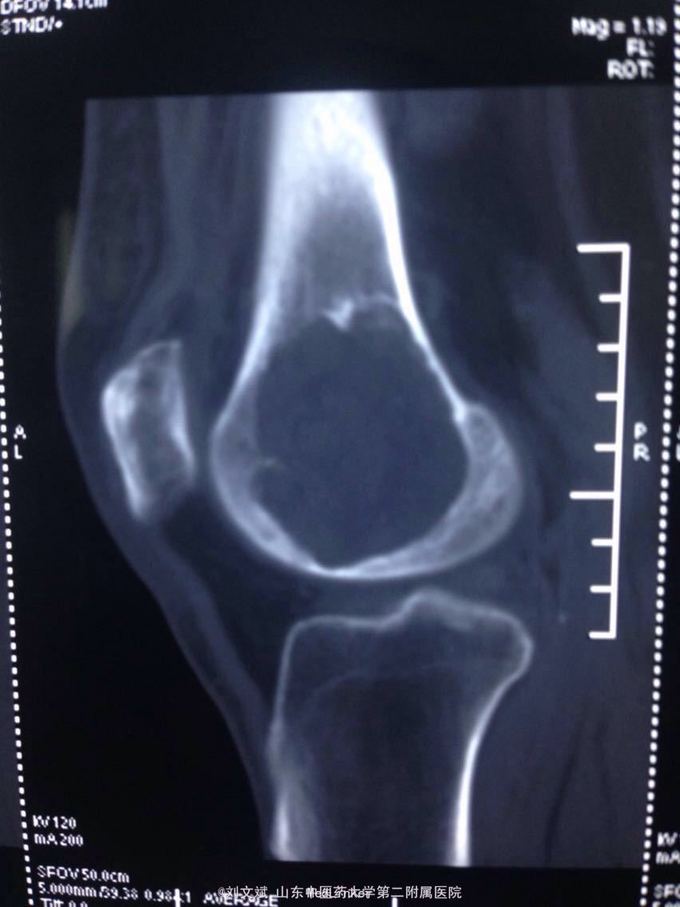

男性51岁,左膝关节疼痛不适10余年。因症状较轻,不影响活动,未曾系统诊治。一月前因扭伤致疼痛加重,拍片检查,见股骨远端骨质异常,进一步行CT示股骨髁占位病变,考虑骨囊肿。既往有高血压,糖尿病病史。近期无低热,体重下降。

诊断:左股骨远端占位 因皮质完整,行手术开窗刮除,自体髂骨及同种异体骨混合植骨填充治疗。切取组织送病理检查

刮除占位组织如图所示,送病理检查了,结果还没回来。 没有全身症状,像是原发灶,骨皮质完整,没有明显骨膜反应请专家们看看,什么可能性比较大? 补上病理结果和术后片子